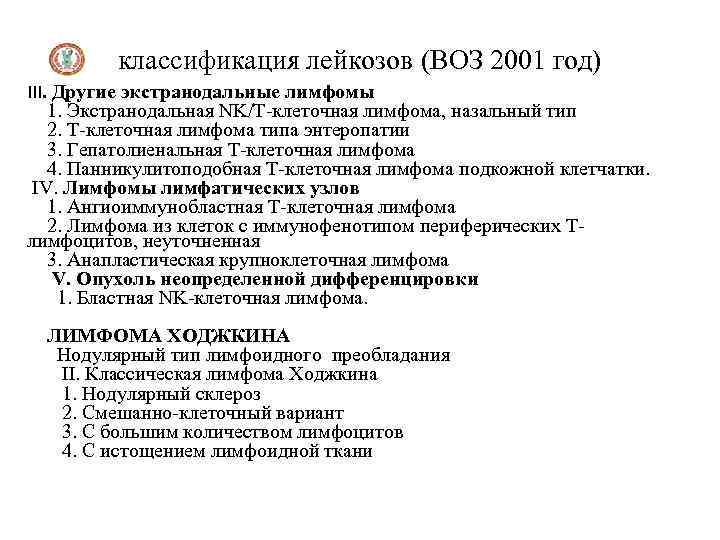

классификация лейкозов (ВОЗ 2001 год) III. В-клеточные лимфопролиферативные процессы с неопределенным опухолевым потенциалом 1. Лимфоматоидный гранулематоз 2. Посттрансплантационное лимфопролиферативное заболевание, полиморфноклеточное Т-КЛЕТОЧНЫЕ ОПУХОЛИ I. Опухоли из предшественников Т-лимфоцитов Т-лимфобластный лейкоз/лимфома из предшественников Т-клеток (острый лимфобластный лейкоз из предшественников Т-клеток). II. Т- и NK-клеточные опухоли с фенотипом зрелых лимфоцитов Лейкозы и первично диссеминированные лимфомы: 1. Т-клеточный пролимфоцитарный лейкоз 2. Т-клеточный лейкоз из крупных гранулярных лимфоцитов 3. Агрессивный NK-клеточный лейкоз 4. Т-клеточный лейкоз/лимфома взрослых Кожные лимфомы 1. Грибовидный микоз 2. Синдром Сезари 3. Первичная кожная крупноклеточная анапластическая лимфома 4. Лимфоматоидный папуллез

классификация лейкозов (ВОЗ 2001 год) III. Другие экстранодальные лимфомы 1. Экстранодальная NK/Т-клеточная лимфома, назальный тип 2. Т-клеточная лимфома типа энтеропатии 3. Гепатолиенальная Т-клеточная лимфома 4. Панникулитоподобная Т-клеточная лимфома подкожной клетчатки. IV. Лимфомы лимфатических узлов 1. Ангиоиммунобластная Т-клеточная лимфома 2. Лимфома из клеток с иммунофенотипом периферических Тлимфоцитов, неуточненная 3. Анапластическая крупноклеточная лимфома V. Опухоль неопределенной дифференцировки 1. Бластная NK-клеточная лимфома. ЛИМФОМА ХОДЖКИНА Нодулярный тип лимфоидного преобладания II. Классическая лимфома Ходжкина 1. Нодулярный склероз 2. Смешанно-клеточный вариант 3. С большим количеством лимфоцитов 4. С истощением лимфоидной ткани